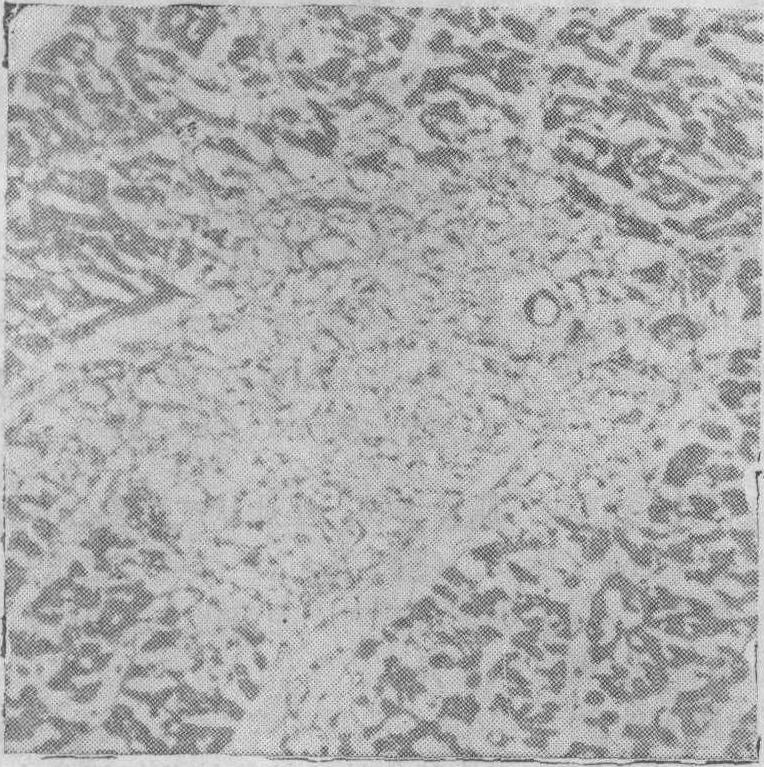

❷本病心肌病变呈灶状或带状分布,病灶之间隔有正常心肌组织。切片经适当染色后,仅低倍放大,病灶即清晰可见。病灶散布于心脏各部,但各处损伤程度不同。总的说来,左室及室间隔重于右室,心室重于心房,心室壁的内层和中层重于外层。和成人相比,小儿心肌病变多相对集中于左室壁的中层或中层偏外。当病变发生于乳头肌或肉柱时,则病变常呈节段性分布(图6),即病灶呈不规则的横带状,与正常心肌组织交替出现。当病灶位于心内膜下时,易见不完全的内膜下保留现象,即紧贴心内膜常见1~2条肌纤维免于坏死。这一特点和缺氧性心肌坏死相似,但与心肌梗塞时比较完整而较厚的内膜下保留现象又不尽相同。心脏的起搏传导系统,和收缩肌纤维一样,也可受累,同样以实质细胞变性、坏死、纤维化为主。

❸心肌病灶分布上最明显的特点是病灶与心室壁内冠状动脉分支的走行有密切关系。心肌坏死灶每围绕心室壁内冠状动脉的分支而分布,这在小儿亚急型特别明显。左室壁有分支型与直进型两种小动脉分支,本病的坏死灶也可见到围绕相应血管的分布,与分支型相当,在心室壁外层和中层有多数小病灶呈树枝状、葡萄状分布(图7),病灶与小动脉、细动脉和终末细动脉相连;与直进型相当,在外、中层可见坏死灶呈套袖状围绕直进型血管,到达内膜下则病变扩大、融合成片成带(图8)。前面提到的乳头肌病灶的节段性分布也与血管密切相关。

图7 病灶沿血管分布。左室壁外、中层的葡萄状病灶(MCT 、低倍)